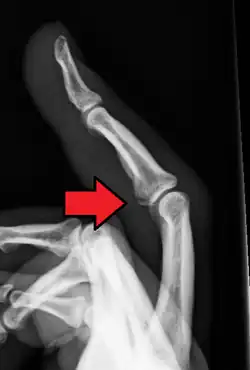

X-ray of an avulsion fracture of the head of the first (thumb) metacarpal on the left hand of a 16-year-old male, images taken one day and seven weeks after the injury, respectively.

If the fracture is small, it is usually sufficient to treat with rest and support bandage, but in more severe cases, surgery may be required. Ice may be used to relieve swelling.[6]

Displaced avulsion fractures are best managed by either open reduction and internal fixation or closed reduction and pinning. Open reduction (using surgical incision) and internal fixation is used when pins, screws, or similar hardware is needed to fix the bone fragment.